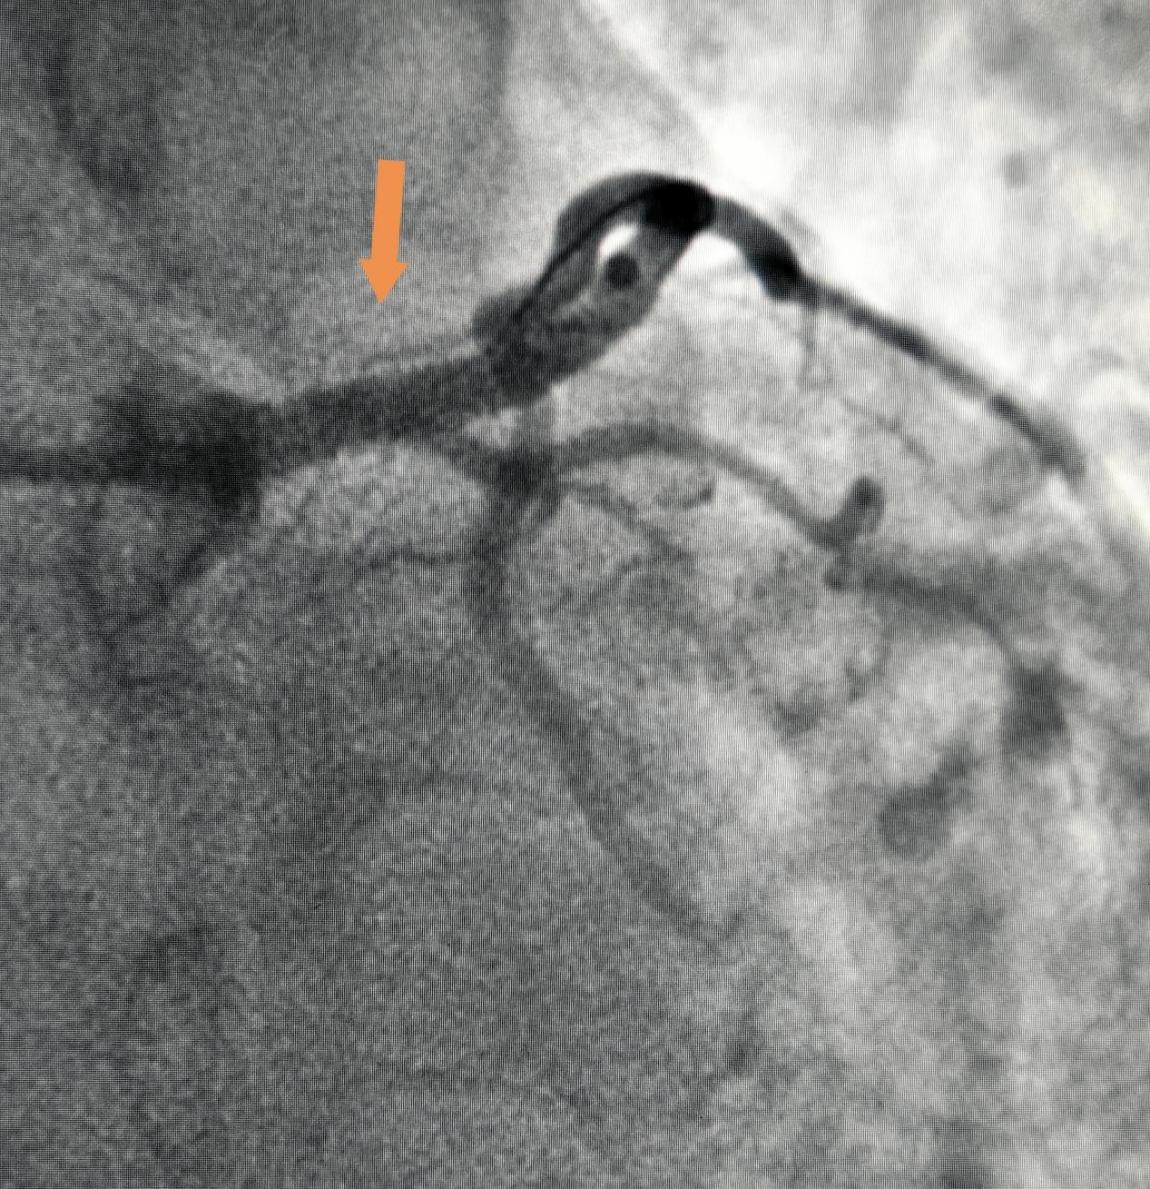

團隊根據超聲測量的血管情況,選擇植入合適的支架,完全覆蓋斑塊,再應用IVUS指導擴張支架,復查IVUS,術后管腔最小直徑僅3.59mm,管腔面積9.98mm2,斑塊負荷達到42%。清楚地顯示植入支架直徑與血管直徑完全匹配,血管通暢,支架貼壁情況良好,無夾層、血腫等并發癥,術后患者恢復良好,胸痛癥狀消失。

術后管腔最小直徑僅3.59mm,管腔面積9.98mm2,斑塊負荷達到42%

治療后血管完全再通